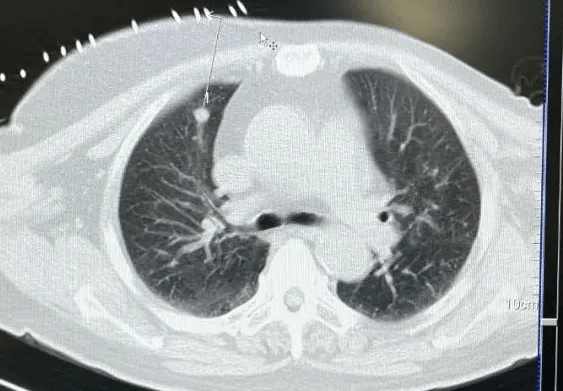

案例一:IQQA®-Guide引导下右肺肿物穿刺活检

术者:介入治疗科于海鹏教授

病例简介:男,82岁,主因“检查发现右肺肿物半月余”入院。PET-CT提示:1.右肺尖肿物,PET显像可见异常放射性浓聚,考虑周围型肺癌,2.纵膈内、腔静脉后、右主支气管及右肺门多发结节,考虑为淋巴结转移,3.右侧胸膜局限性结节,不除外恶性。

上图:IQQA术前eOrganMap三维重建及手术规划

上图:IQQA®-Guide术中全程3D影像实时定位、引导、跟踪、引导及监控,避开重要血管,精准到达肿瘤内预设的穿刺点

上图:CT扫描确认后,行活检取样